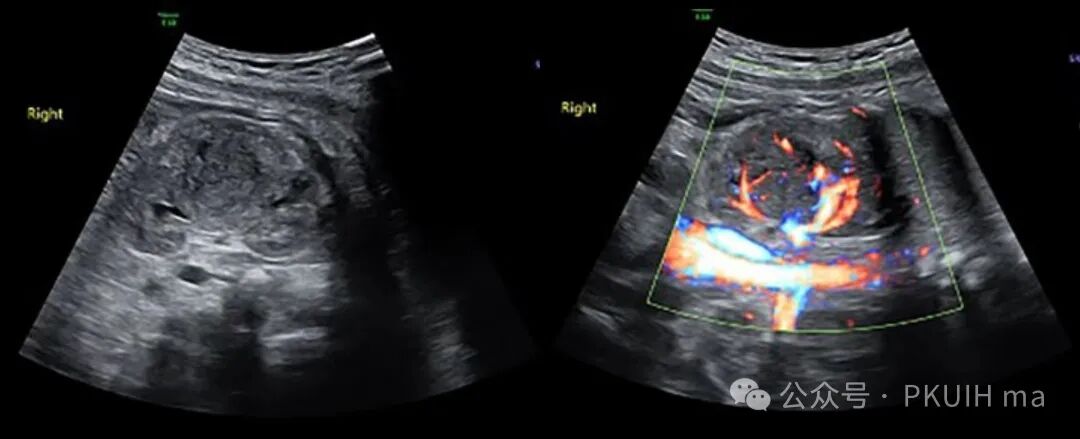

上图是来自文献的图片,显示胎儿一侧肾巨大的肾母细胞瘤